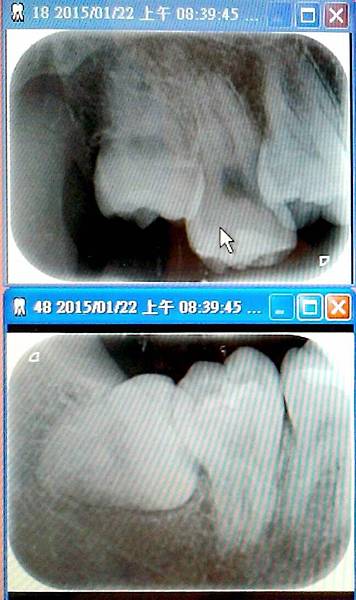

照X光片真的比拔牙還痛,底片一直頂到肉,

共照六次,看到護士一直跟我說抱歉,我也認了

X光片的上圖為右上智齒,下圖為右下智齒